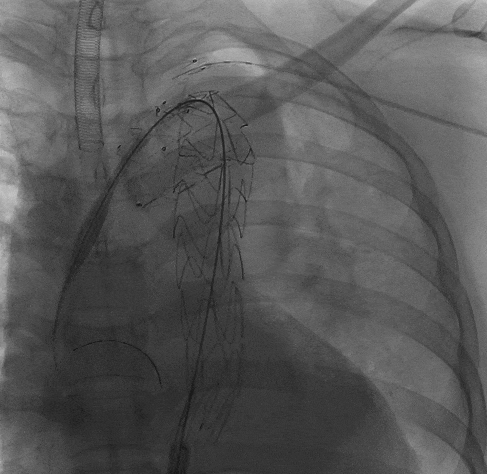

2、随后撤出长鞘,从右侧股动脉沿超硬导丝上推输送系统至降主动脉,在褪下输送系统外管后,上推支架,在定位精准后,撤掉部分支架软鞘露出分支支架,助手配合牵拉分支导丝,使分支支架进入LSA。

动脉长鞘怎么置入宁波市第二医院血管外科运用Castor®单分支支架结合长鞘建立导丝通路的方法治疗Stanford B型胸主动脉夹层一例_https://www.jmylbn.com_新闻资讯_第8张

褪下部分软鞘后,牵拉分支支架进入LSA

动脉长鞘怎么置入宁波市第二医院血管外科运用Castor®单分支支架结合长鞘建立导丝通路的方法治疗Stanford B型胸主动脉夹层一例_https://www.jmylbn.com_新闻资讯_第9张

褪下剩余软鞘